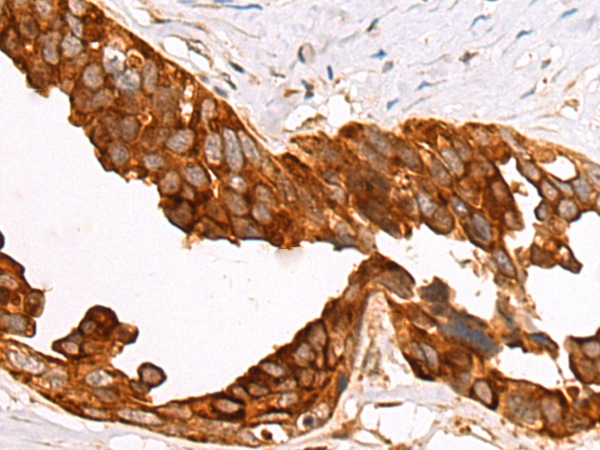

The image is immunohistochemistry of paraffin-embedded Human colorectal cancer tissue using P03577(RHPN2 Antibody) at dilution 1/85. (Original magnification: ×200) |